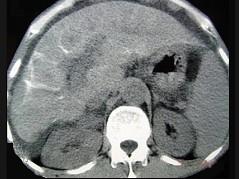

问题 男性,63岁,腹胀、双下肢浮肿、乏力、食欲不振,影像所见如下图,最佳的诊断是 ( )

选项 A.酒精性肝硬化 B.血吸虫肝硬化 C.肝炎后肝硬化 D.局限性脂肪肝 E.原发性肝癌

答案 B